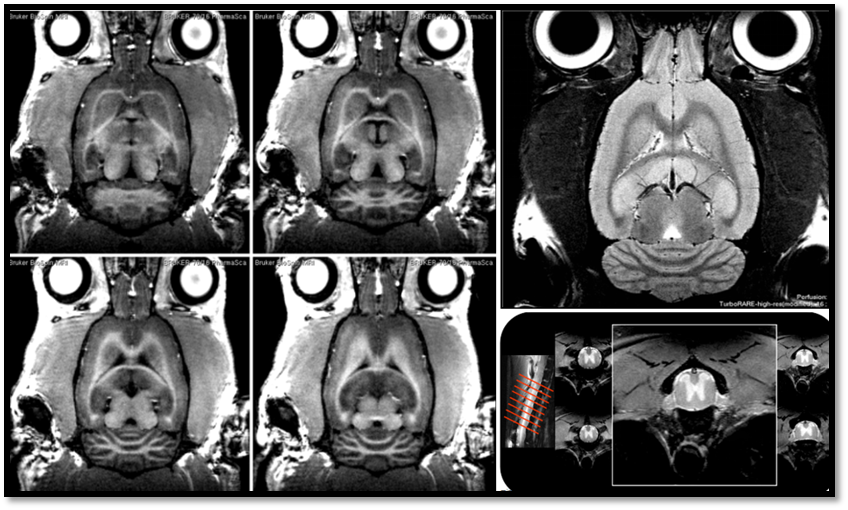

日期:2018-06-26(保障科通讯)为进一步提升科研能和水平,推进基础与临床学科的交叉研究,今年我所从德国Bruke公司引进了动物磁共振成像仪(型号:BioSpec70/20USR),并于本月在仁济医院正式装机启用,成为国内第四家、上海第二家拥有高场强小动物活体成像的研究平台。

BioSpec70/20USR凭借其强大的梯度系统和超高场的磁体,不仅具有对软组织、大脑、神经、心血管、关节、肺部、腹部等极高的分辨力和优秀的成像效果,同时还可在活体器官的细胞水平或亚细胞水平进行定性与定量成像。该仪器主要应用于小动物疾病模型早期诊断、肿瘤疗效的观察和研究、药物研究、脑功能成像、共振波谱成像及脑科学与神经功能分子影像学等研究,这为进行小动物磁共振前沿性研究奠定了坚实的基础和强有力的支撑。

该设备硬件设备配置齐全,包括小鼠体线圈、小鼠头线圈、大鼠体线圈、大鼠头线圈、各种表面线圈、气体麻醉装置、小动物生理监控和同步触发扫描装置、热水循环装置等。与其搭载的ParaVision 6是临床MRI软件中的最新标配,其全新直观的工作流程为用户提供了优化检查方案选择、主动参数冲突处理、全自动系统优化、快速数据采集以及图像后处理等功能。除此之外,该机器还可实现实时扫描优化、实时射频脉冲计算、在线图像重建、用于高分辨率3D成像的快速64位多核图像重建、任意长方体或椭圆体匀场、3D图像可视化和分析、脉冲序列开发等诸多高级功能,结合其完备的硬件实施,共同为小动物MRI研究提供强大的技术支撑。

附:部分图像展示

图2 高分辨活体大脑、脊髓结构像

图3 高分辨水分子弥散加权像

图4 高分辨率磁敏感图像,显示微小淀粉样变斑块,显示能力达到染色切片水平

图5波谱分析技术,可精确量化代谢产物及神经递质

图6 颅内微小血管显示